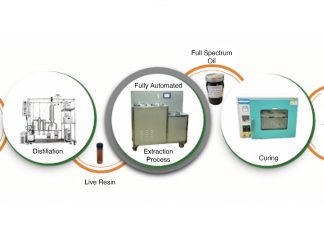

From each sample, the team took approximately 1000 single cells to identify those that were able to grow and were resistant to current chemotherapy. Using state-of-the-art RNA sequencing, the researchers were able to see that neurexin-1 was expressed at high levels in these cancer stem-like cells.